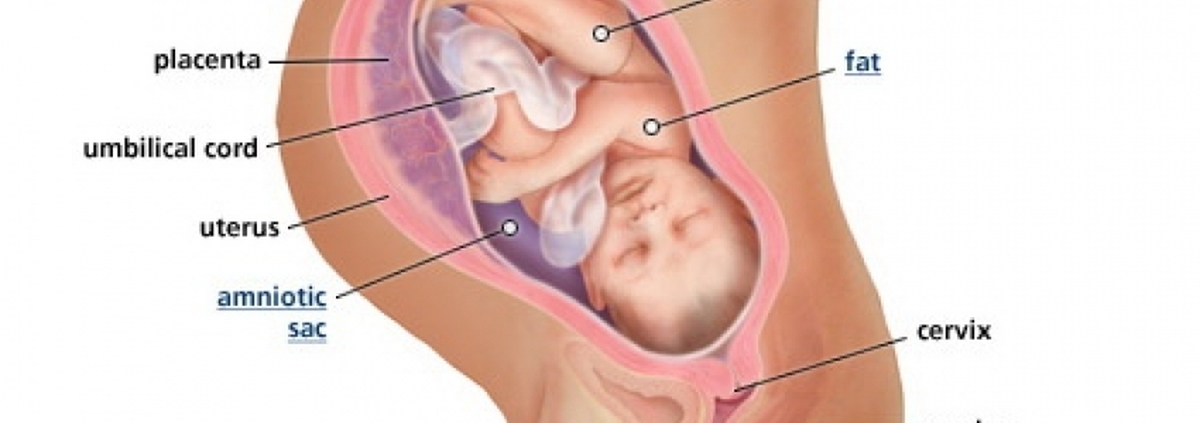

Плод 39 Недель Фото

Плод 39 Недель Фото 100 фото